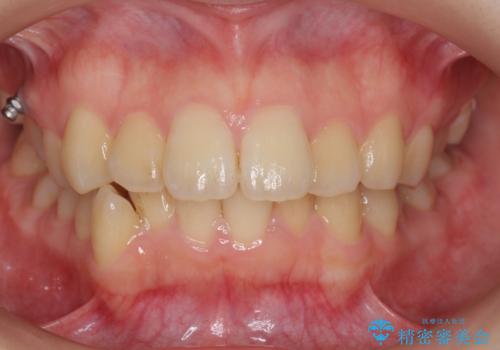

- 歯のがたつきを主訴に来院。

左右とも奥歯のがたつきがあり、左奥はすれ違っていました。

また、右奥は反対咬合になっていました。

インビザライン治療は主に奥歯のかみ合わせが大きな問題がない場合は特に問題なく終了しますが、今回のケースのように奥歯のかみ合わせが悪い場合、しっかり治らないことがあります。

患者様が気づかない範囲で妥協して終わるということをせず、しっかり奥歯に部分矯正を用いて大きな問題を解決してからインビザライン治療に入りました。

下の前歯を一本抜歯しています。(抜歯の本数は最小限にしています。)